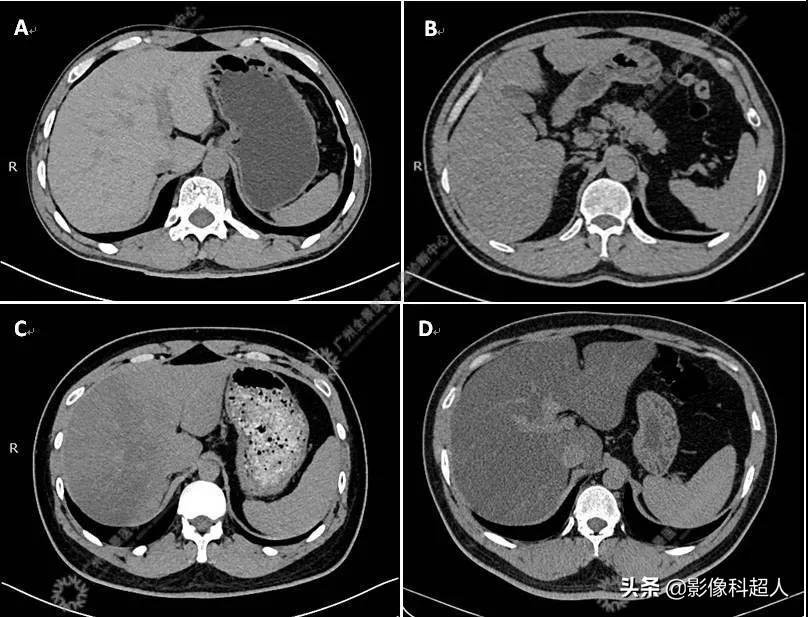

脂肪肝的CT诊断与分度

脂肪肝的CT表现主要为肝脏密度减低,呈弥漫性或局部肝实质密度减低,其密度与浸润脂肪含量密切相关(负相关);随着肝细胞内脂肪含量越高,对应的CT值越低。脂肪肝的CT诊断与分度标准主要可分为以下两种:

1、肝/脾CT密度比值法

在正常肝脏,肝的CT密度应大于同一层面脾的CT密度。当肝脏密度降低,肝/脾CT比值< 1时,即可诊断为脂肪肝。肝/脾CT比值为0.7~1.0 时为轻度脂肪肝;肝/脾CT比值为0.5~0.7时为中度脂肪肝;肝/脾CT比值为0.5 以下时为重度脂肪肝。

2、肝脏与肝内血管相对密度法

在正常肝脏,肝实质密度应大于肝血管密度。当肝脏实质密度降低,肝实质与肝血管CT相对密度发生变化。肝组织与肝内血管相比呈等密度时,为轻度脂肪肝;肝组织密度低于肝血管(肝血管反转显示),为中度脂肪肝;肝组织密度明显低于肝血管密度时,为重度脂肪肝。

A:正常;B:轻度脂肪肝;C:中度不均匀脂肪肝;D:重度脂肪肝。